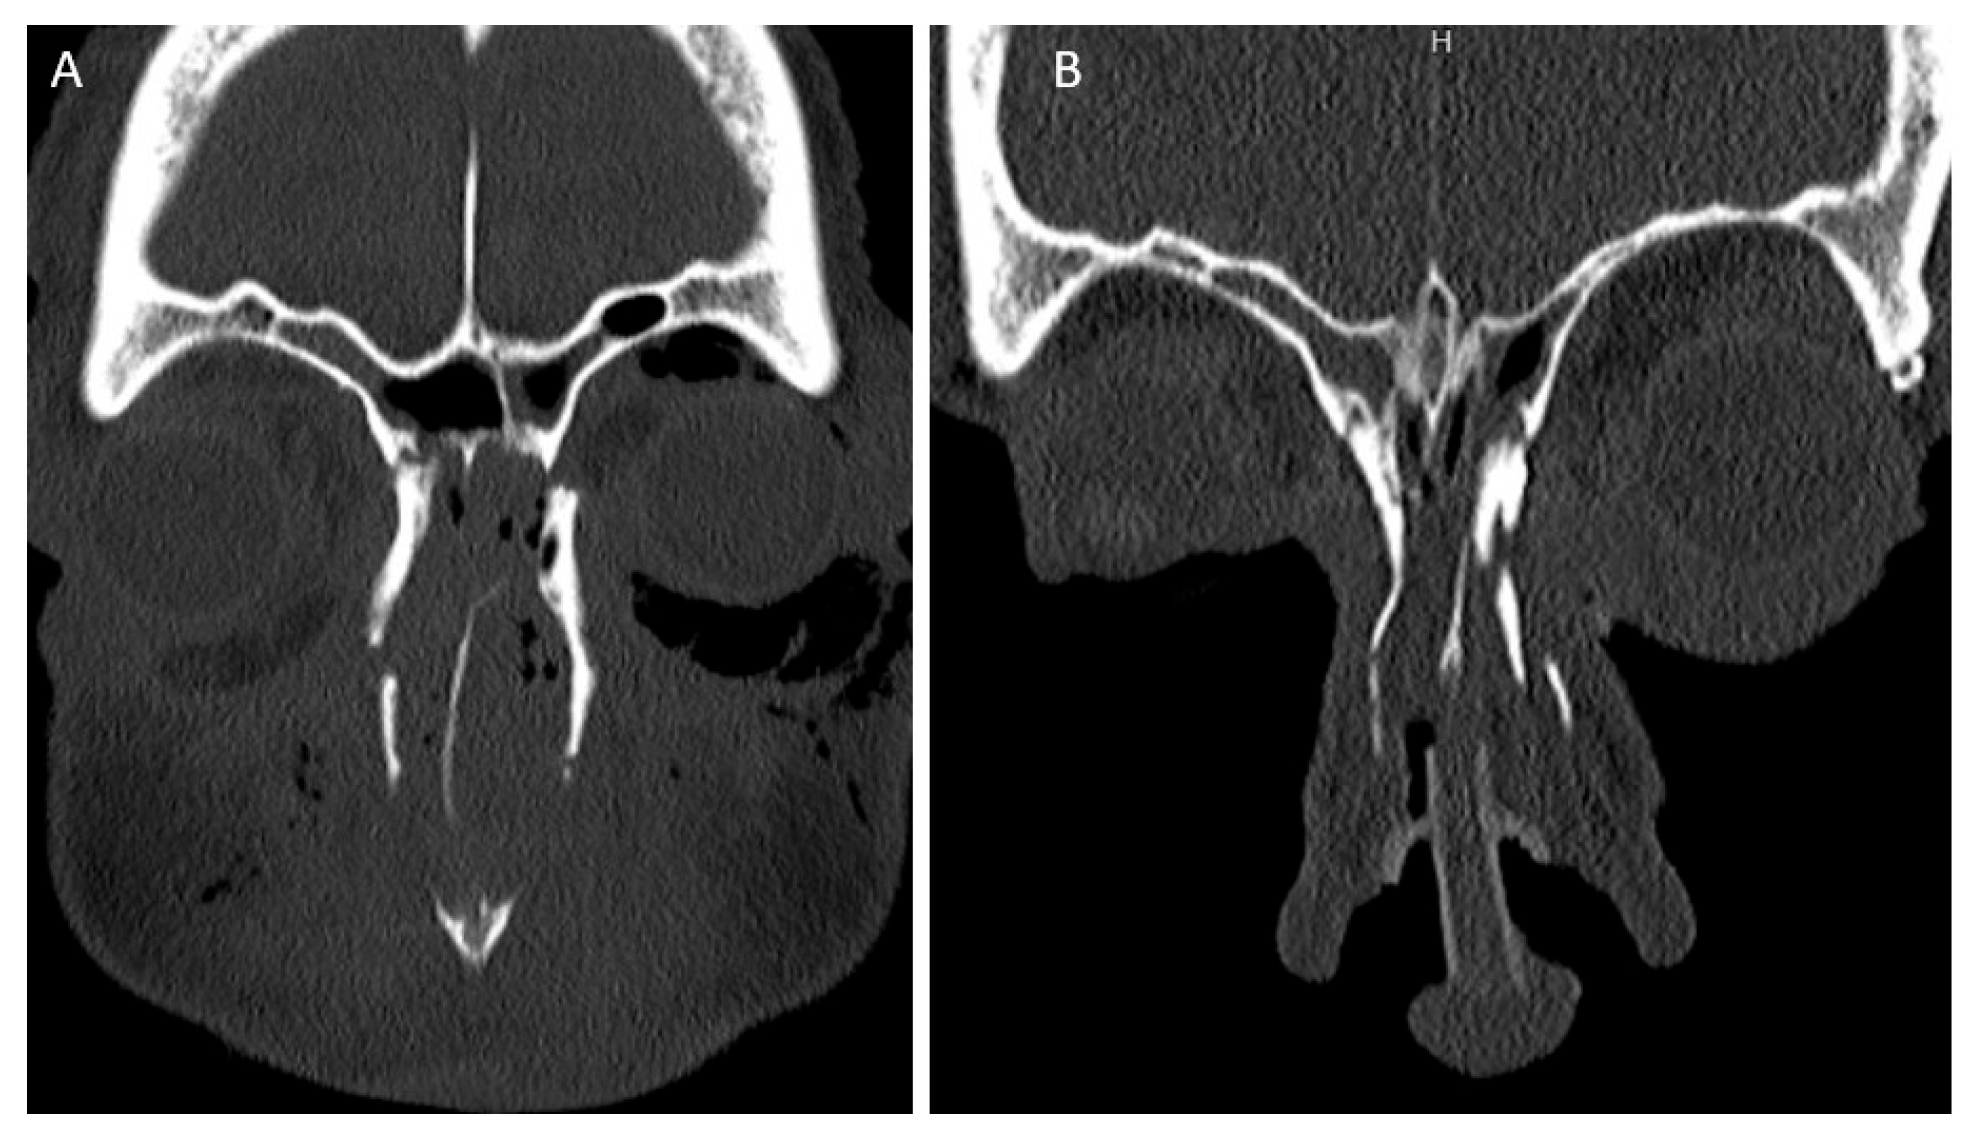

Both intercanthal and interpupillary distances were measured on pre-operative scans and available post-operative CT scans. Representative scans are shown in Figure 1. These measurements were compared to normative values for intercanthal and interpupillary distance obtained from the literature for the population [7,8].

Figure 1. Pre-(A) and post-(B) operative reduction in canthal fragment (fixation not completely shown).